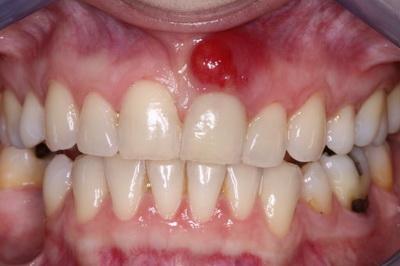

Фото 2. Небольшая шишка на десне над коронкой зуба, однако впоследствии она может привести к воспалительному процессу.